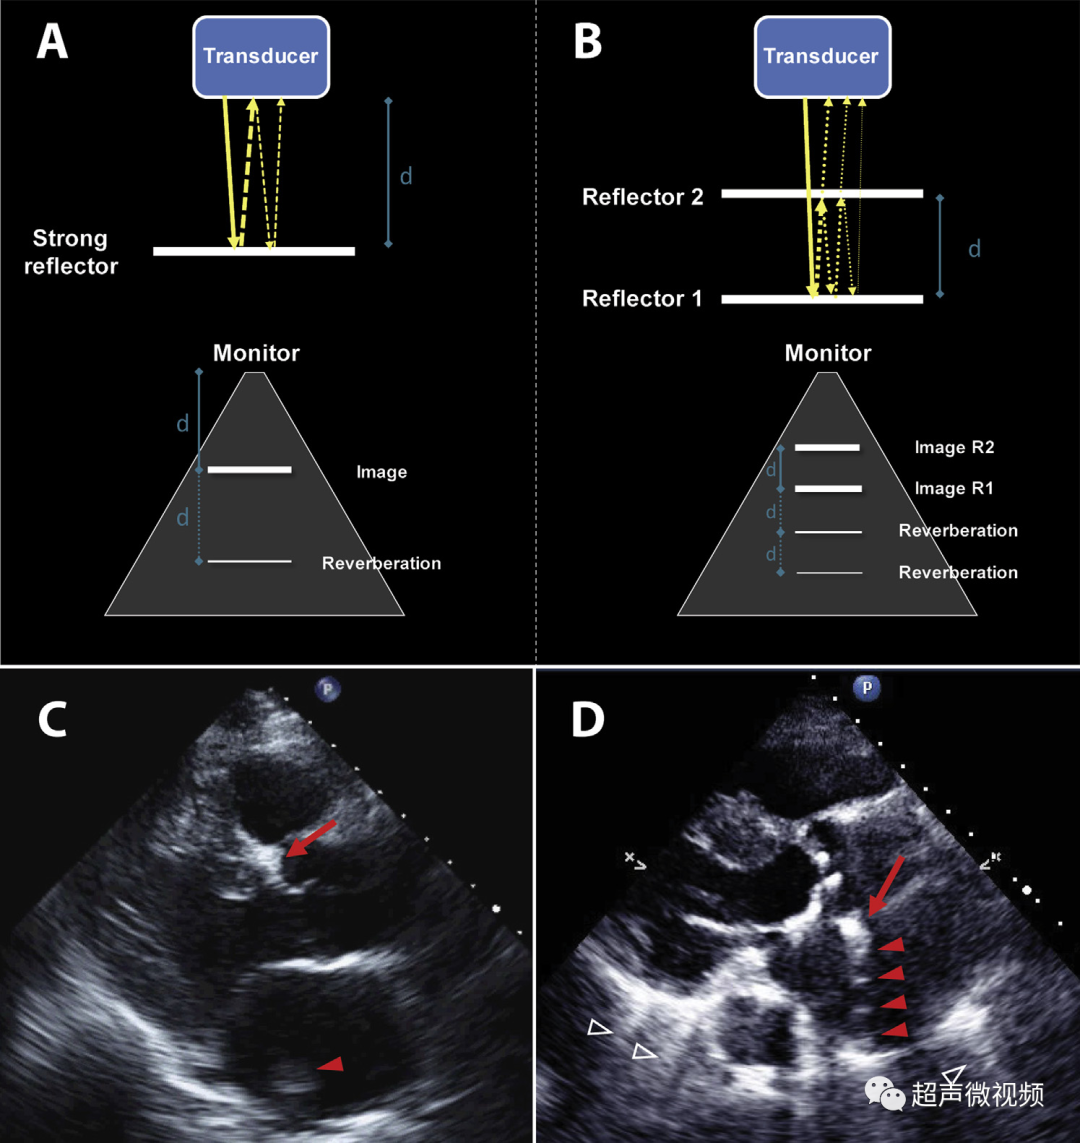

2、混响伪像

混响伪像违反了回波在一次反射后返回探头的假设。理论上,当超声波从探头发射时,反射波直接传输回探头,进行一次往返。实际上,第一次反回到探头的声波又从探头的平滑面再次反射,在两倍于第一反射器的距离处产生伪像。在心动周期期间,伪影的运动与真实结构的运动平行,但幅度更大(通常是两倍)(视频1-3)。

图2 (A,B)混响假象的理论成因(视频1)。第二反射界面可以是探头本身(A ),导致到探头两倍距离处的混响,或者是位于第一反射器上方的另一个强反射器(B)。

(C)胸骨旁长轴切面中的混响伪影似为左心房中的肿块(箭头)。对肿块的详细分析表明,它是钙化主动脉瓣环的反射(箭头),肿块正好出现在距离传感器两倍的距离处(视频2)。

(D)“多层”主动脉钙化(箭头)下方典型的“阶梯式”反射(实心箭头),作为第一和第二反射层(视频3)。也可以观察到强反射心包下的彗尾反射(空箭头)。